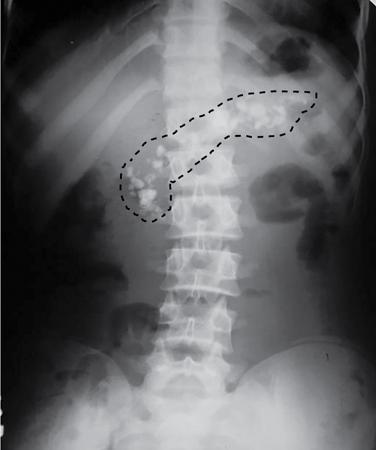

UNDERSTANDING THE ADULT ABDOMINAL RADIOGRAPH: TECHNIQUES AND INTERPRETATION Tanvi Modi Radiography of the abdomen is a common practice for the evaluation of abdominal organs. The anatomy and pathology of digestive, hepatobiliary and genitourinary systems can be assessed using radiographs, either as a stand-alone practice or as a primary imaging modality followed by contrast studies, ultrasound or cross-sectional imaging. In addition, abnormalities of the musculoskeletal or integumentary system can also be deduced on the basis of abdominal radiographs. This chapter intends to give an overview on the techniques and positioning in abdominal radiography as well as interpretation of normal and abnormal features. While superior imaging modalities such as ultrasound, computed tomography (CT), magnetic resonance imaging, capsule endoscopy and the likes have taken over abdominal imaging by and large, radiography still holds a pivotal role in certain situations and conditions, such as: The standard abdominal radiograph is taken in supine position and anteroposterior projection. This is also popularly known as the KUB (kidneys-ureters-bladder) radiograph. Previously, supine as well as erect radiographs were performed in all patients; however, this is not commonly done due to high-radiation dose. For all indications of abdominal radiography, including acute abdomen, supine radiographs are sufficient in terms of radiographic diagnosis, with the exception of perforation for which an erect chest or lateral decubitus radiograph can be performed if there is clinical suspicion. Patient should lie supine on the imaging table with median sagittal plane at right angles to the table and coincident with the midline of the table (Fig. 7.1.1.1). The body is divided into equal right and left halves by the median sagittal which passes through the sagittal suture of the skull. Pelvis should be adjusted so that the anterior superior iliac spines are equidistant from the table top. Gonadal shields, in the case of male patients, should be placed with the upper edge of the shield at the level of pubic symphysis. Although rarely used for female patients, these should be positioned between the anterior superior iliac spines and the pubic symphysis. The centre point of the image receptor should be approximately located at a point 1 cm below the line joining the iliac crests. The X-ray beam should be in a vertical direction, perpendicular to the table top and image receptor at the centre point. Collimation should be such that the soft tissue and subcutaneous region along lateral aspects of the abdominal cavity should be covered within the image. Also, the superior extent involving diaphragm and inferior extent involving the inferior pubic rami is important to look for any lower chest pathologies or any inguinal hernia. 35 × 43 cm (14 × 17 inches) in portrait orientation. On an average, abdominal radiograph exposes a patient to a dose of approximately 1.5 mSv, which is equivalent to 75 chest radiographs or 1/6th dose of a standard CT of the abdomen. The entrance skin dose is approximated to be 4 mGy. At such an effective dose, the additional lifetime risk of fatal cancer is 1 in 30,000. The exposure time is kept short. Patient is asked to exhale completely and hold their breath, with exposure taken at this point of full expiration to ensure imaging of abdominal organs in their natural positions. Modifications of this technique can be made depending on patient habitus and clinical condition. Kilovoltage peak (kVp) should be set to allow adequate visualization of abdominal soft tissue structures as well as semiopaque renal and biliary calculi. Average kVp is set at 70–85 kV. 102 cm (40 inches) Grids are commonly used to reduce scatter radiation. Placement of side marker on the image receptor at the time of radiographic exposure is essential. Bowel pattern depiction should be such that there is minimal lack of sharpness. Standard guidelines for abdominal radiography dictate that the radiograph should extend from the diaphragm up to the level of inferior pubic rami and must include the lateral abdominal wall musculature. The abdomen is divided into four quadrants on the basis of two perpendicular lines (Fig. 7.1.1.7). The vertical line passes through the mid sagittal plane and crosses the umbilicus and symphysis pubis. The horizontal line is a transverse line across the umbilicus at 90 degrees to the vertical line and is situated at the level of L4–L5 intervertebral disc. The quadrants are as follows: Another division system is dividing the abdominopelvic cavity into nine regions using two vertical and two horizontal planes (Fig. 7.1.1.8). The vertical planes, also known as the right and left lateral planes, are parallel to the midsagittal plane between midline and anterosuperior iliac spines on either side. Of the two horizontal planes, the upper transpyloric plane is at the level of lower border of L1 and the lower transtubercular plane is at the level of L5. The nine regions are: On a standard radiograph, the exposure should be such that the stomach, bowel loops, outlines of liver, spleen, kidneys, psoas muscles should be well identified. Also, lumbar transverse processes should be seen. Arch of the pubic symphysis should be visible to evaluate bladder region. A well-centred film without rotation will demonstrate bilaterally symmetrical lower ribs, iliac wings, ischial spines and obturator foramina. Different structures seen on an abdominal radiograph can be classified into five basic densities: Identification of different structures depends on the relative degree of contrast between their densities. The demarcation is clearer in chest and is diminished in abdomen due to relative similar soft tissue density of various structures. On a normal radiograph, relatively large amounts of gas in stomach and colon with minimal small bowel gas can be seen. Further, colonic gas can vary from negligible to extensive, mimicking obstruction pattern; however, usually the gas is enough to delineate colonic haustral pattern. Faecal matter gives a mottled appearance to colonic gas. Short-air fluid levels on an erect radiograph may be seen even in normal cases. The normal appearance of small bowel loops on an abdominal radiograph follows the rule of threes: Stomach is seen in the left upper quadrant and is visualized when distended with air. It is commonly seen extending from T11 to L2 level. Common feature identifying the stomach is the fundal gas which is usually seen as an air fluid level within the gastric lumen. Small bowel loops are distributed to the centre of the abdominal cavity and large bowel loops are peripheral. Duodenum is predominantly situated in right upper quadrant. It extends to left upper quadrant in the region of duodenojejunal flexure. Jejunum occupies the left upper and lower quadrants and is easily identified due to the presence of thick, numerous, closely spaced valvulae conniventes (Fig. 7.1.1.9A). The ileum occupies both lower quadrants and extends into right upper quadrant. Ileum has few and less prominent valvulae as compared to jejunum (Fig. 7.1.1.9B). Ascending and descending colon are retroperitoneal and have relatively fixed positions along lateral aspect of the abdominal cavity on either side. Transverse and sigmoid colon, on the other hand, may have a variable position due to their mobility along mesocolon and redundant pattern. These can be identified with confidence on account of haustrations and faecal matter (Fig. 7.1.1.10). Haustrations are usually well seen in ascending and transverse colon and poorly delineated beyond splenic flexure. Caecum is in the right lower quadrant, though it may be mobile or pulled up. Rectal gas is usually seen in the midline at the level of pelvis and its presence rules out large bowel obstruction. All these positions may vary due to anatomical conditions such as malrotation or pathological conditions, for example volvulus. Liver, spleen and renal outlines cannot be completely traced with precision due to the overlap by bowel loops. On a frontal projection, the liver appears as a triangular structure occupying right and left hypochondrium and epigastric region. Occasionally, the right lobe may be seen extending lower than the right renal shadow. This is a normal variant known as Reidel’s lobe. Gall bladder is situated in the posterior and inferior region of the liver and any pathology of the gall bladder should be looked for in this region. On a lateral radiograph, the gall bladder is anterior to the midcoronal plane. This helps in distinguishing gall bladder calculi from renal calculi, which will be more posteriorly situated. Spleen is seen in left upper quadrant/left hypochondrium, flushed to left lower ribs and left hemidiaphragm. Pancreas is present in the epigastric region (right and left upper quadrants) and is usually not identified in the absence of a pathology. The kidneys are bean-shaped retroperitoneal organs which are seen on either side of the vertebral column and lateral to psoas muscles. Due to the presence of liver on the right side, this kidney is slightly lower in position as compared to its contralateral counterpart. The visualization of kidneys on radiographs is facilitated by the surrounding fatty capsule. Kidneys lie between T11–12 and L2 level, with left kidney 1 cm higher than the right. Psoas muscle shadow can be normally seen along lateral aspect of lumbar spine bilaterally and is mildly concave (Fig. 7.1.1.11). Abdominal wall muscles are not routinely assessed on radiography; however, inclusion of lateral abdominal wall (muscles as well as subcutaneous plane) is a must while performing radiography. The flank stripe or the properitoneal fat stripe is a fat density linear concavity seen along lateral abdominal wall (Fig. 7.1.1.11). It is bound by the paracolic gutters and air-filled ascending and descending colon. All the solid organs in the abdomen are identified due to the fat density outlining them. Distortion of these fat lines helps in identifying organomegaly or focal mass lesions. The dome of urinary bladder is outlined by fat, which aids in differentiating its density from other soft tissue structures of the pelvis. Not all calcifications seen on abdominal radiograph are abnormal. Some may depict age-related changes such as vascular calcifications involving abdominal aorta, pelvic vessels, splenic artery in the region of left upper quadrant. Within the pelvis, phleboliths may be seen and mistaken for urinary calculi. Assessment of lumbosacral spine, iliac bones and femoral heads can be made on the basis of plain radiography. Degenerative changes may be commonly seen. Lower ribs can also be evaluated for pathologies. Dilated small bowel loops with rounded soft tissue density in midline over umbilical region suggests obstruction secondary to umbilical hernia. Pneumoperitoneum must be looked for in all cases of acute abdomen. While erect chest and left lateral decubitus radiographs can detect even 1 mL of free air, there are multiple signs on supine radiograph to suggest this diagnosis, for example Rigler’s sign, falciform ligament sign, football sign (Figs. 7.1.1.24 and 7.1.1.25). Retroperitoneal perforation may demonstrate air outlining psoas muscles and retroperitoneal organs. Small amount of free air may persist in the abdominal cavity up to 3 weeks after surgery, although it usually resolves within a week. Clinical history is important in such cases. Air foci within the bowel wall may represent bowel ischaemia/strangulation. Linear gas patterns in right hypochondrium may be due to two causes, that is pneumobilia and pneumoporta. The former can be seen normally postbiliary surgery, sphincterotomy, ERCP or in the case of abnormal fistulous communication between bowel and biliary tree (Fig. 7.1.1.26A). Pneumoporta (Fig. 7.1.1.26B) is a red flag and warrants further investigation to look for conditions such as mesenteric ischaemia and toxic megacolon. Pneumobilia is more centrally located whereas air shadows in pneumoporta are seen reaching up to periphery of liver. Air foci over renal shadows (Fig. 7.1.1.27), gall bladder or pancreas, in the absence of recent procedural history, suggest fulminant infection and mandate urgent intervention. Central midline calcific foci between T9 and T12 vertebrae can be attributed to calcific pancreatitis (Fig. 7.1.1.28). In the left upper quadrant, areas of calcification seen involving a shrunken spleen may be seen in autosplenectomy. In right upper quadrant, calcified gall stones may be seen. These tend to be small, multiple, uniformly circumscribed and ring-like in appearance with central translucency (Fig. 7.1.1.29A). Mercedes Benz sign, a triradiate pattern of gas lucency, is associated with gallstones. In contrast, renal calculi are more commonly solitary, irregular, of homogenous density, conform to renal calyceal or pelvic outline (Fig. 7.1.1.29B) and are sometimes of staghorn configuration. On lateral view, the gall stones are more anteriorly located as compared to renal calculi, which may be partly superimposed on lumbar vertebrae. Ureteric calculi tend to overlap bony structures such as lumbar transverse processes (Fig. 7.1.1.29B) or sacroiliac joints. Extensive or patchy, curvilinear calcification of gall bladder wall is known as porcelain gall bladder which is often associated with malignant transformation. Calcification involving adrenal glands may be secondary to infection or haematoma, or a congenital condition known as Wolman’s disease where there is bilateral involvement. Discontinuous discrete midline tram track calcification in the abdomen may indicate atherosclerotic changes in abdominal aorta and branch vessels. However, when the calcification is in a globular pattern and seen below the level of L2 vertebra, aortic aneurysm should be suspected (Fig. 7.1.1.30). Appendicoliths, though not commonly seen, may sometimes be detected in right iliac region. Pelvic calcifications: vesical calculi, distal ureteric or vesicoureteric junction calculi, calcified fibroids, ovarian dermoid with tooth-like calcifications (Fig. 7.1.1.31) may be the cause of abdominal pain and should be diligently looked for. Vesical calculi are usually more large and central in location whereas calcification due to fibroids may be more lateral. Schistosomiasis is another cause of bladder wall calcification, as is calcification of bladder tumours. Phleboliths tend to be bilaterally symmetrical, with a lucent centre unlike ureteric calculi. While it is believed that phleboliths are located below the level of ischial spines and ureteric calculi above, this is not always true and should be confirmed with CT. Fluid may collect adjacent to properitoneal fat line, forming a linear soft tissue density separating the fat line from the ascending or descending colon. Hellmer’s sign demonstrates medial displacement of lateral edge of liver (hepatic angle), due to fluid collection or ascites. Gross ascites may appear as generalized abdominal haziness or diffuse increased density of pelvis. Abscesses can involve any solid organ and in such cases may be difficult to demonstrate on plain radiography alone. Enlargement of organ or faint gas densities within can be suggestive of the same. In the case of peritoneal abscess, mottled density due to air, fluid and necrotic contents point towards this diagnosis, especially in right iliac fossa in association with appendicitis. Retroperitoneal abscess, similar to any retroperitoneal mass, may cause displacement of retroperitoneal structures (Fig. 7.1.1.32). Subdiaphragmatic abscesses may show concomitant ipsilateral pleural effusion (Fig. 7.1.1.33). These should be differentiated from Chilaiditi syndrome. Fluid and soft tissue lesions present with the same density on radiographs. While it is difficult to characterize the lesion and organ of origin, clues for the same can be provided by organomegaly (Fig. 7.1.1.34), distortion of fat surrounding solid organs, displacement of bowel loops or solid organs. For example, a retroperitoneal lesion may cause anterior or inferior displacement of kidney, a pelvic mass may cause upward displacement of small bowel loops. Different densities such as fat or calcification may help in identifying organ of origin (e.g. fat and tooth densities seen in ovarian dermoid). Convexity of margins of psoas muscle on an abdominal radiograph can be due to haematoma, abscess or intramuscular tumour. Radiographs are performed for the initial diagnosis of foreign body in the abdomen including type, number of foreign bodies, location, size and shape (Fig. 7.1.1.35). Radiolucent foreign bodies such as wood, plastic, chicken bones will not be easily identified on radiography. Low kVp (65–70 kVp) can increase contrast and help identify these objects. In addition to an abdominal radiograph, chest radiography is also performed to exclude aspiration or oesophageal location of foreign body. Ingested or introduced foreign bodies may cause complications such as obstruction, perforation, fistula formation and sepsis. Hence, once their presence is confirmed, follow up radiography must be performed until they are eliminated. One must look for fractures/dislocation injuries involving the vertebrae or pelvic bones, especially after history of trauma. Lucent expansile lesions or sclerotic bony deposits which represent neoplasms, absent pedicle sign in cases of metastasis, metabolic bony changes such as rugger jersey appearance, Paget’s disease, arthropathies such as ankylosing spondylitis with bamboo spine appearance and sacroiliitis (Fig. 7.1.1.36) are some of the conditions which may be diagnosed based on an abdominal radiograph. Overlap of bowel loops over iliac blades may lead to a misdiagnosis of lucent lesions and should be evaluated with caution. Basal pneumonia may be the cause of acute abdominal pain and should be looked for in abdominal radiography. Similarly, pleural effusion, pericardial effusion, calcified pleural plaques, achalasia, interstitial fibrosis are few other findings that can be seen in lower chest on an abdominal radiograph. Basilar atelectasis can give a deceptive appearance of pneumoperitoneum (Fig. 7.1.1.37). Surgical clips, commonly in right hypochondrium after cholecystectomy, drainage tubes, ventriculoperitoneal shunts, femoral line catheters, IVC filters, stents (vascular, renal, biliary) (Fig. 7.1.1.38), stoma bags, contraceptive devices are some structures that may be seen in an abdominal radiograph. Correct knowledge of patient history and normal locations of these structures prevents misdiagnosis. Certain artefacts may be projected upon the radiograph due to surface structures such as trouser buttons, body piercing, sequins over clothing and should not be considered as a pathology. Multiple skin surface nodules in cases of neurofibromatosis, soft tissue focal swellings, such as abscesses, lipomas, haematomas, desmoid tumours and malignant lesions may be incidentally seen on radiography. These can be further evaluated using ultrasound or CT. Subcutaneous emphysema is another finding that may be seen in lower abdominal wall secondary to retroperitoneal perforation or diffusely along abdominal wall in the case of bowel perforation (Fig. 7.1.1.39). Foreign bodies such as bullets and pins may be seen lodged in abdominal wall. A systematic approach to abdominal radiographs is important for accurate diagnosis as follows: Despite the development of newer techniques for imaging of the abdomen, plain radiography still holds an important place in the initial assessment of acute abdomen. Positive and negative findings on an abdominal radiograph can direct further investigation. Ideal positioning, recognition of normal appearances and keen scrutiny for pathologies is a sine qua non for radiologists reading a plain film of the abdomen. OESOPHAGOGRAM Padma V. Badhe, Vikram Reddy, Sultan Moinuddin Shaukatali, Zillani Alam, Ravi Varma, Abhishek Bairy, Dasari Ravikiran, Revati Tekwani, Soniya Patankar, Megha Nair, Gautham Shankar Oesophagogram is the process of obtaining radiological images and simultaneous motion recording to evaluate function and disorders of pharynx, oesophagus and proximal stomach. Oesophagogram is usually done primarily to evaluate dysphagia. Some of the common indications are oesophageal motility disorders, strictures, gastro-oesophageal reflux disease (GERD) and suspected masses. It can also be used to detect uncommon anomalies like vascular rings/slings and aberrant anatomy. It also helps to evaluate further in cases where there is inability to pass upper GI scope. Double-contrast oesophagogram is mainly indicated in early mucosal disease like erosion, polyp, infection and tumours. If a motility disorder is suspected, dynamic technique (e.g. videofluoroscopy) is used for dysphagia or aspirations in cases of stroke, neuromuscular disorders, post head and neck surgery or radiation. Barium oesophagogram is contraindicated in suspected cases of perforation and tracheoesophageal fistula, aspiration, rarely if there is hypersensitivity to barium suspensions. It is also contraindicated in suspected oesophageal perforation where a water-soluble contrast agent is more suitable. However, ionic water-soluble contrast agent is better avoided in cases of aspiration or fistula with airway. The contrast examination of the pharynx is dangerous in cases of acute epiglottitis and must be ruled out on plain radiograph. An 80% w/v barium suspension is used in full column views. However, 200%–250% w/v barium suspensions is usually required for mucosal relief films. The barium sulphate mixture is fed to the patient either by spoon, by glass, or through a drinking straw, depending on its consistency. In videofluoroscopy, the pharyngeal phase of swallowing is usually safer with barium pudding than with thick barium and safer with thick barium than with thin barium. However, if the major abnormality is poor pharyngeal contraction leading to stasis in the piriform sinus (and epiglottic tilt is normal), a thin liquid is safer. Epiglottic motility is better assessed with thin barium because thick barium often obscures the epiglottic tip. Fluoroscopic equipment capable of cine fluoroscopy and capability for rapid sequence spot images (high frame rate) is needed for this examination, Barium suspension, straw, glass, Lead apron and radiation protective equipment. The patients are instructed to fast after midnight before the day of the examination. The pharynx should be made as dry as possible during the examination as high-density barium adheres to dry pharyngeal mucosa. Activities like smoking, chewing gum and lozenges must be abstained before the procedure as they impair barium coating by increasing the salivary secretion. Regular oral medications must be taken with sips of water; however, insulin must be skipped on the morning of examination. The major principles of a good oesophagogram includes mucosal coating, distension and projection. A routine oesophagogram consists of screening of the oral, pharyngeal and oesophageal phases of swallowing, single and double-contrast examination of pharynx, single contrast, double-contrast and mucosal relief views of the oesophagus. In cases of dysphagia, the examination is tailored depending on whether the symptoms are either pharyngeal or oesophageal and initial fluoroscopic findings. If patients’ symptoms are suggestive of oral or pharyngeal disorder then pharynx is evaluated first. Similarly, if patient is suspected to have thoracic oesophageal disease then, double-contrast examination of the oesophagus is performed before the pharyngeal evaluation. During an oesophagogram the positioning of the patient varies according to the type of examination (Table 7.1.2.1).